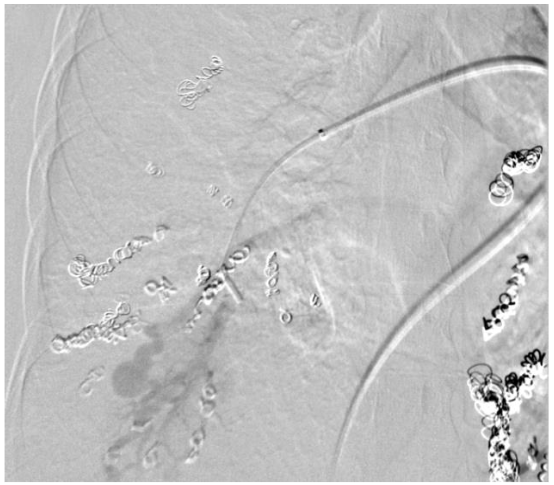

The patient is a 31-year-old gravida 4, para 2 who presented for routine obstetric care at 30 weeks gestation. She has a known history of HHT and PAVM, with prior embolization of two left-sided PAVMs. The patient was referred for evaluation of her pulmonary vascular status. At 30 weeks, the patient was noted to have a significant increase in the size of her PAVMs. The recommended imaging studies were significant for numerous bilateral PAVM and she underwent placement of 10 total vascular coils ante retrograde. Unfortunately, the largest PAVM measured 32mm and was located within the left lingula, where a feeding vessel could not be identified. The next largest PAVM measured 17 mm (located in the right upper lobe) and 23 mm (located in the right lower lobe), both of which were successfully treated.